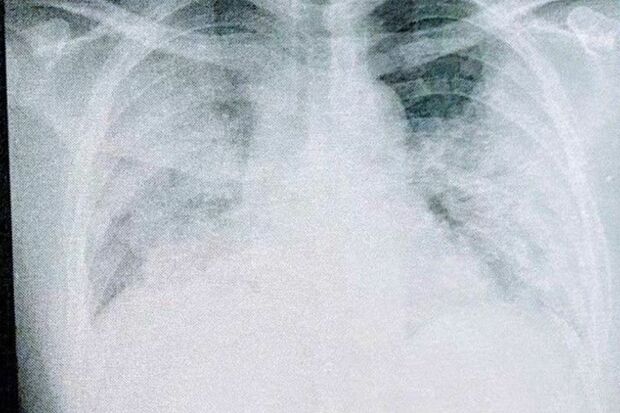

8月12日、入院した当日に撮った肺のレントゲン写真(写真:取材者提供/東洋経済オンライン)

[写真 4/7枚目] 8月12日、入院した当日に撮った肺のレントゲン写真(写真:取材者提供/東洋経済オンライン)